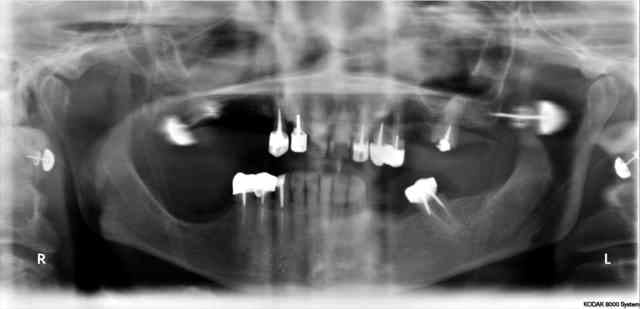

CCM 13 12 11 21 22 23 24 +27

CCM 43 44 45 + 36

STELLITE HAUT ET BAS

sinon il a quoi dans la bouche ce patient????